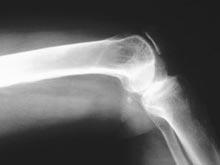

Донорские банки костной ткани - будущее современной ортопедии, уверены эксперты

Многие люди с поражениями костей и суставов могут получить новую жизнь с пересадкой костной ткани. И ключевую роль здесь играют костные банки, где в специальных морозильных камерах хранится собранный во время операций тщательно измельченный, обработанный...